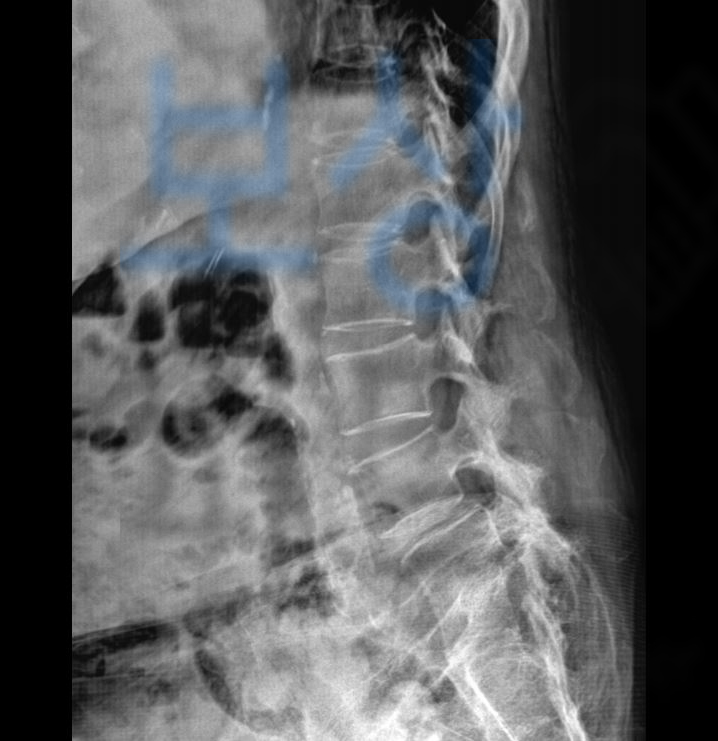

병원에서 엑스선 검사와 mri 검사 등 정밀 검사를 시행해 보니, 요추압박골절 진단을 받게 되었죠.

L5 부위의 골절 s32060 와 천골의 골절 s3210 진단을 받아 특별한 치료 없이 허리보조기 착용하며 침대에서 안정을 취하고 요양하는 보존치료를 진행하게 되었습니다.

의뢰인의 mri 검사 기록지를 보시면

Acute compression fracture, L5, S1 즉 급성 척추압박골절 요추 5번, 천추 1번 진단을 받았습니다. 보험 약관에 보시면 보험사에서 인정하는 척추 장해 부위는 경추에서 흉추, 요추, 제 1천추까지 입니다.

“척추체”의 압박골절만 해당되며 그 외 극돌기, 횡돌기, 갈비뼈 혹은 미추 즉 꼬리뼈골절은 최근 개정된 약관 기준으로 척추의 장해에 해당하지 않습니다.